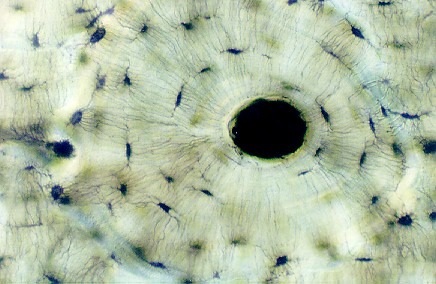

This shows the architecture of compact bone which is designed to nourish and regulate osteocytes and bone matrix. It can be remodeled all throughout life to withstand stress. Identify the circular vessels in the middle of bone running circumferentially around the vessels. These are Haversian canals. They run along the length of the long bone and provide major vessel supply to the osteocytes.

Vessels that connect with those in the Haversian canals run perpendicularly or obliquely to the course of the Haversian canals. These are in Volkmann's canals. Find an example of each on these photos.

Look at the layers of bone and osteocytes running around the Haversian canal. Focus up and down and you can see tiny channels, like spider legs, extending from oblong lacunae. The osteocytes are sitting in the lacunae and the canals are canaliculi, which interconnect the lacunae with the major vessels. This series of channels allows the osteocyte to be nourished and regulated.